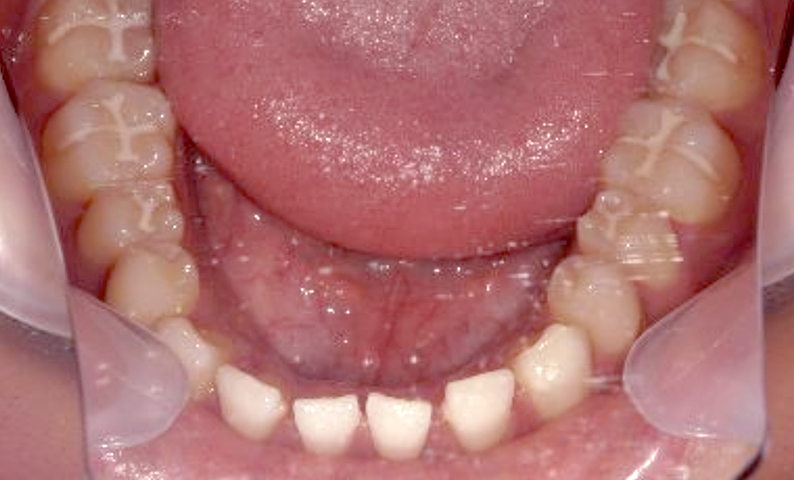

大人になって「すきっ歯」になった?

大人になってから「すきっ歯」になることがあります。

加齢や歯周病などにより、歯茎が下がったり、どこかの歯を失ったままにしておくと、スペースが余って「すきっ歯」になります。

永久歯のすきっ歯は、いくつかの問題を引き起こすことがあるため、できるだけ早く当院にご相談いただくことをおすすめします。